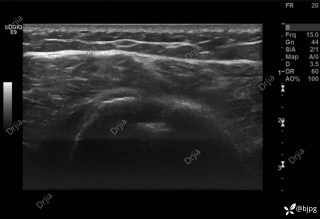

反思 | 赶高铁时一过性晕厥的老年男性

昨天值班遇到的一例晕厥病例,差点漏诊,而最终的解法,始于最简单而质朴的查体。国庆中秋双节的最后一天,8号的早上8点,抢救室床旁晨交班,病人依旧是多而重,交到6床,一个刚入室不久的病人,准备去做CT,夜班医师汇报病史:69岁男性,本次因“头晕伴一过性晕厥1小时”为主诉入抢,1小时前于高铁站因即将赶不上高铁走路快时突发头晕,伴一过性晕厥,约3-4分钟后清醒,清醒后诉今晨未吃早餐,已服用降压药物,仍有头晕头痛、四肢乏力等不适,无胸闷胸痛,无畏寒发热,无咳嗽咳痰,无恶心呕吐,无肢体麻木,无视物模糊等不适,路人拨打120送至我院急诊就诊。既往高血压,长期服用氨氯地平+福辛普利,血压控制一般;糖尿病,长期